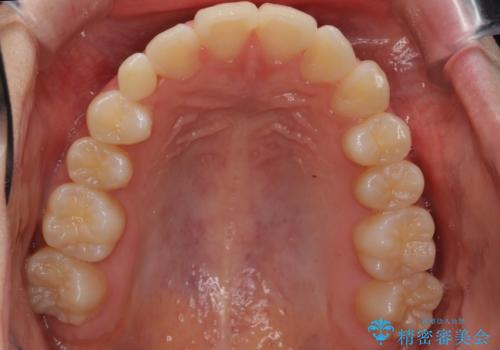

前歯のがたつき 乳歯を抜かずに矯正

- 前歯のがたつきを主訴に来院。

右上に乳歯が残っていましたが、後継永久歯がないため、抜かずに矯正しました。

乳歯の部分が反対咬合でしたが、歯列矯正で被蓋が改善するように移動させました。

右上の乳歯は移動させましたが、幸い矯正後にぐらつくこともなく、そのまま抜けるまで使うことにしました。